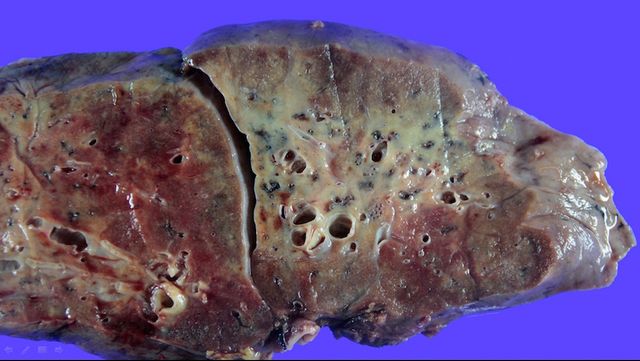

Як виглядають легені, уражені COVID-19: фото не для слабкодухих

Лікарі з Південної Кореї показали знімки легені пацієнта з COVID-19. Це виглядає дійсно страхітливо.

Коронавірус починає розмножуватися на клітинах епітелію, в першу чергу – верхніх дихальних шляхів. Таким чином він проникає в нижню частину легенів і вражає бронхіоли (частина бронхів, що веде безпосередньо в альвеоли, що відповідають за газообмін).

В результаті починається запалення, альвеоли заповнюються рідиною і не можуть виконувати свою функцію. На знімках комп'ютерної томографії цей процес видно як "матове скло" – білясті напівпрозорі ділянки. Чим їх більше, тим сильніше пошкоджені легені і тим менше у людини шансів дихати самостійно.

Наступний етап ураження легень у медиків називається ефект бруківки". На знімках стає чітко видно сітчастий малюнок. Після цього, як правило, настає консолідація плями "матового скла". З напівпрозорих вони стають просто білими. Це саме по собі не погано, але якщо при цьому площа "матового скла" продовжує рости, це привід для тривоги.

Причому нерідко виявляється, що навіть при безсимптомному COVID-19 легені можуть бути серйозно вражені.